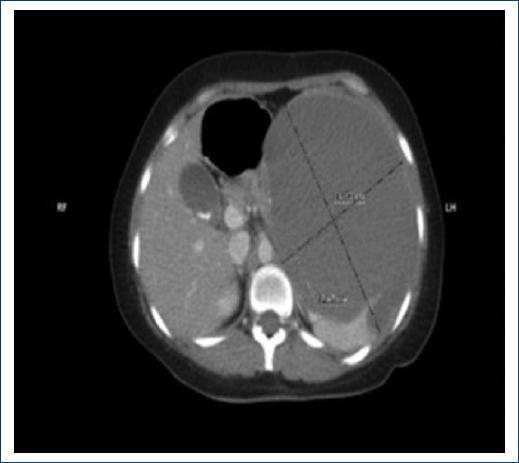

A 33-year-old woman presented with abdominal pain of 2 weeks of evolution located in the flank and left hypochondrium, of sudden onset, continuous of an intensity of 5/10, without radiation, accompanied by nausea without vomiting, she went to the emergency department of the Regional High Specialty Hospital of Ixtapaluca, State of Mexico, Mexico. Laboratories were taken with leukocytes of 7 400, hemoglobin 14.3 g/dL, platelet 246 103/μL, absolute neutrophils 6.5 103/μL, absolute lymph 0.56 103/μL, absolute eosinophils 0.02 103/μL, absolute basophils 0.04 103/μL, absolute monocytes 0.28 103/μL. Subsequently, abdominal tomography was performed that reported a splenic complex cyst of 16.5 × 16.7 × 12.4 cm in its major axes with a volume of 1786 mL that it conditions compression and displacement of the spleen, stomach, splenic angle of the colon, pancreas, and elevation of the hemidiaphragm (Fig. 1).

Figure 1 Presence of cystic lesion in the splenic gland with 16.5 × 16.7 × 12.4 cm in its major axes with a volume of 1786 mL.